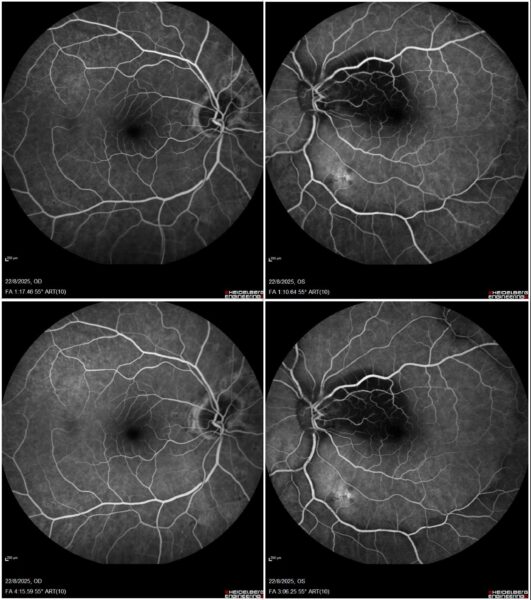

Fundus fluorescein angiography (FFA) showed extensive macular hypofluorescence and a single atrophic lesion in the left eye – between the inferior vascular arcades – without significant change in fluorescence through the angiographic phases (Figure 3).

Figure 3: Bilateral 55° field FFA (Heidelberg Engineering®) featuring extensive macular hypofluorescence and a single, non-exudative posterior pole lesion in the left eye, without significant change in fluorescence through the early- (top) and late-phase (bottom) angiograms.